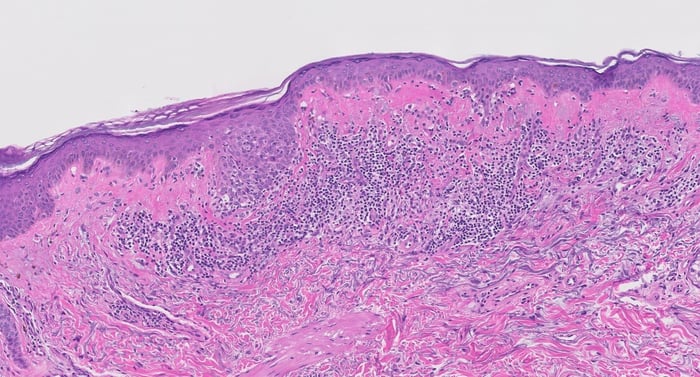

Histopathology images:

This lesion actually turned out to be metaplastic bone, a benign mimic of melanoma.